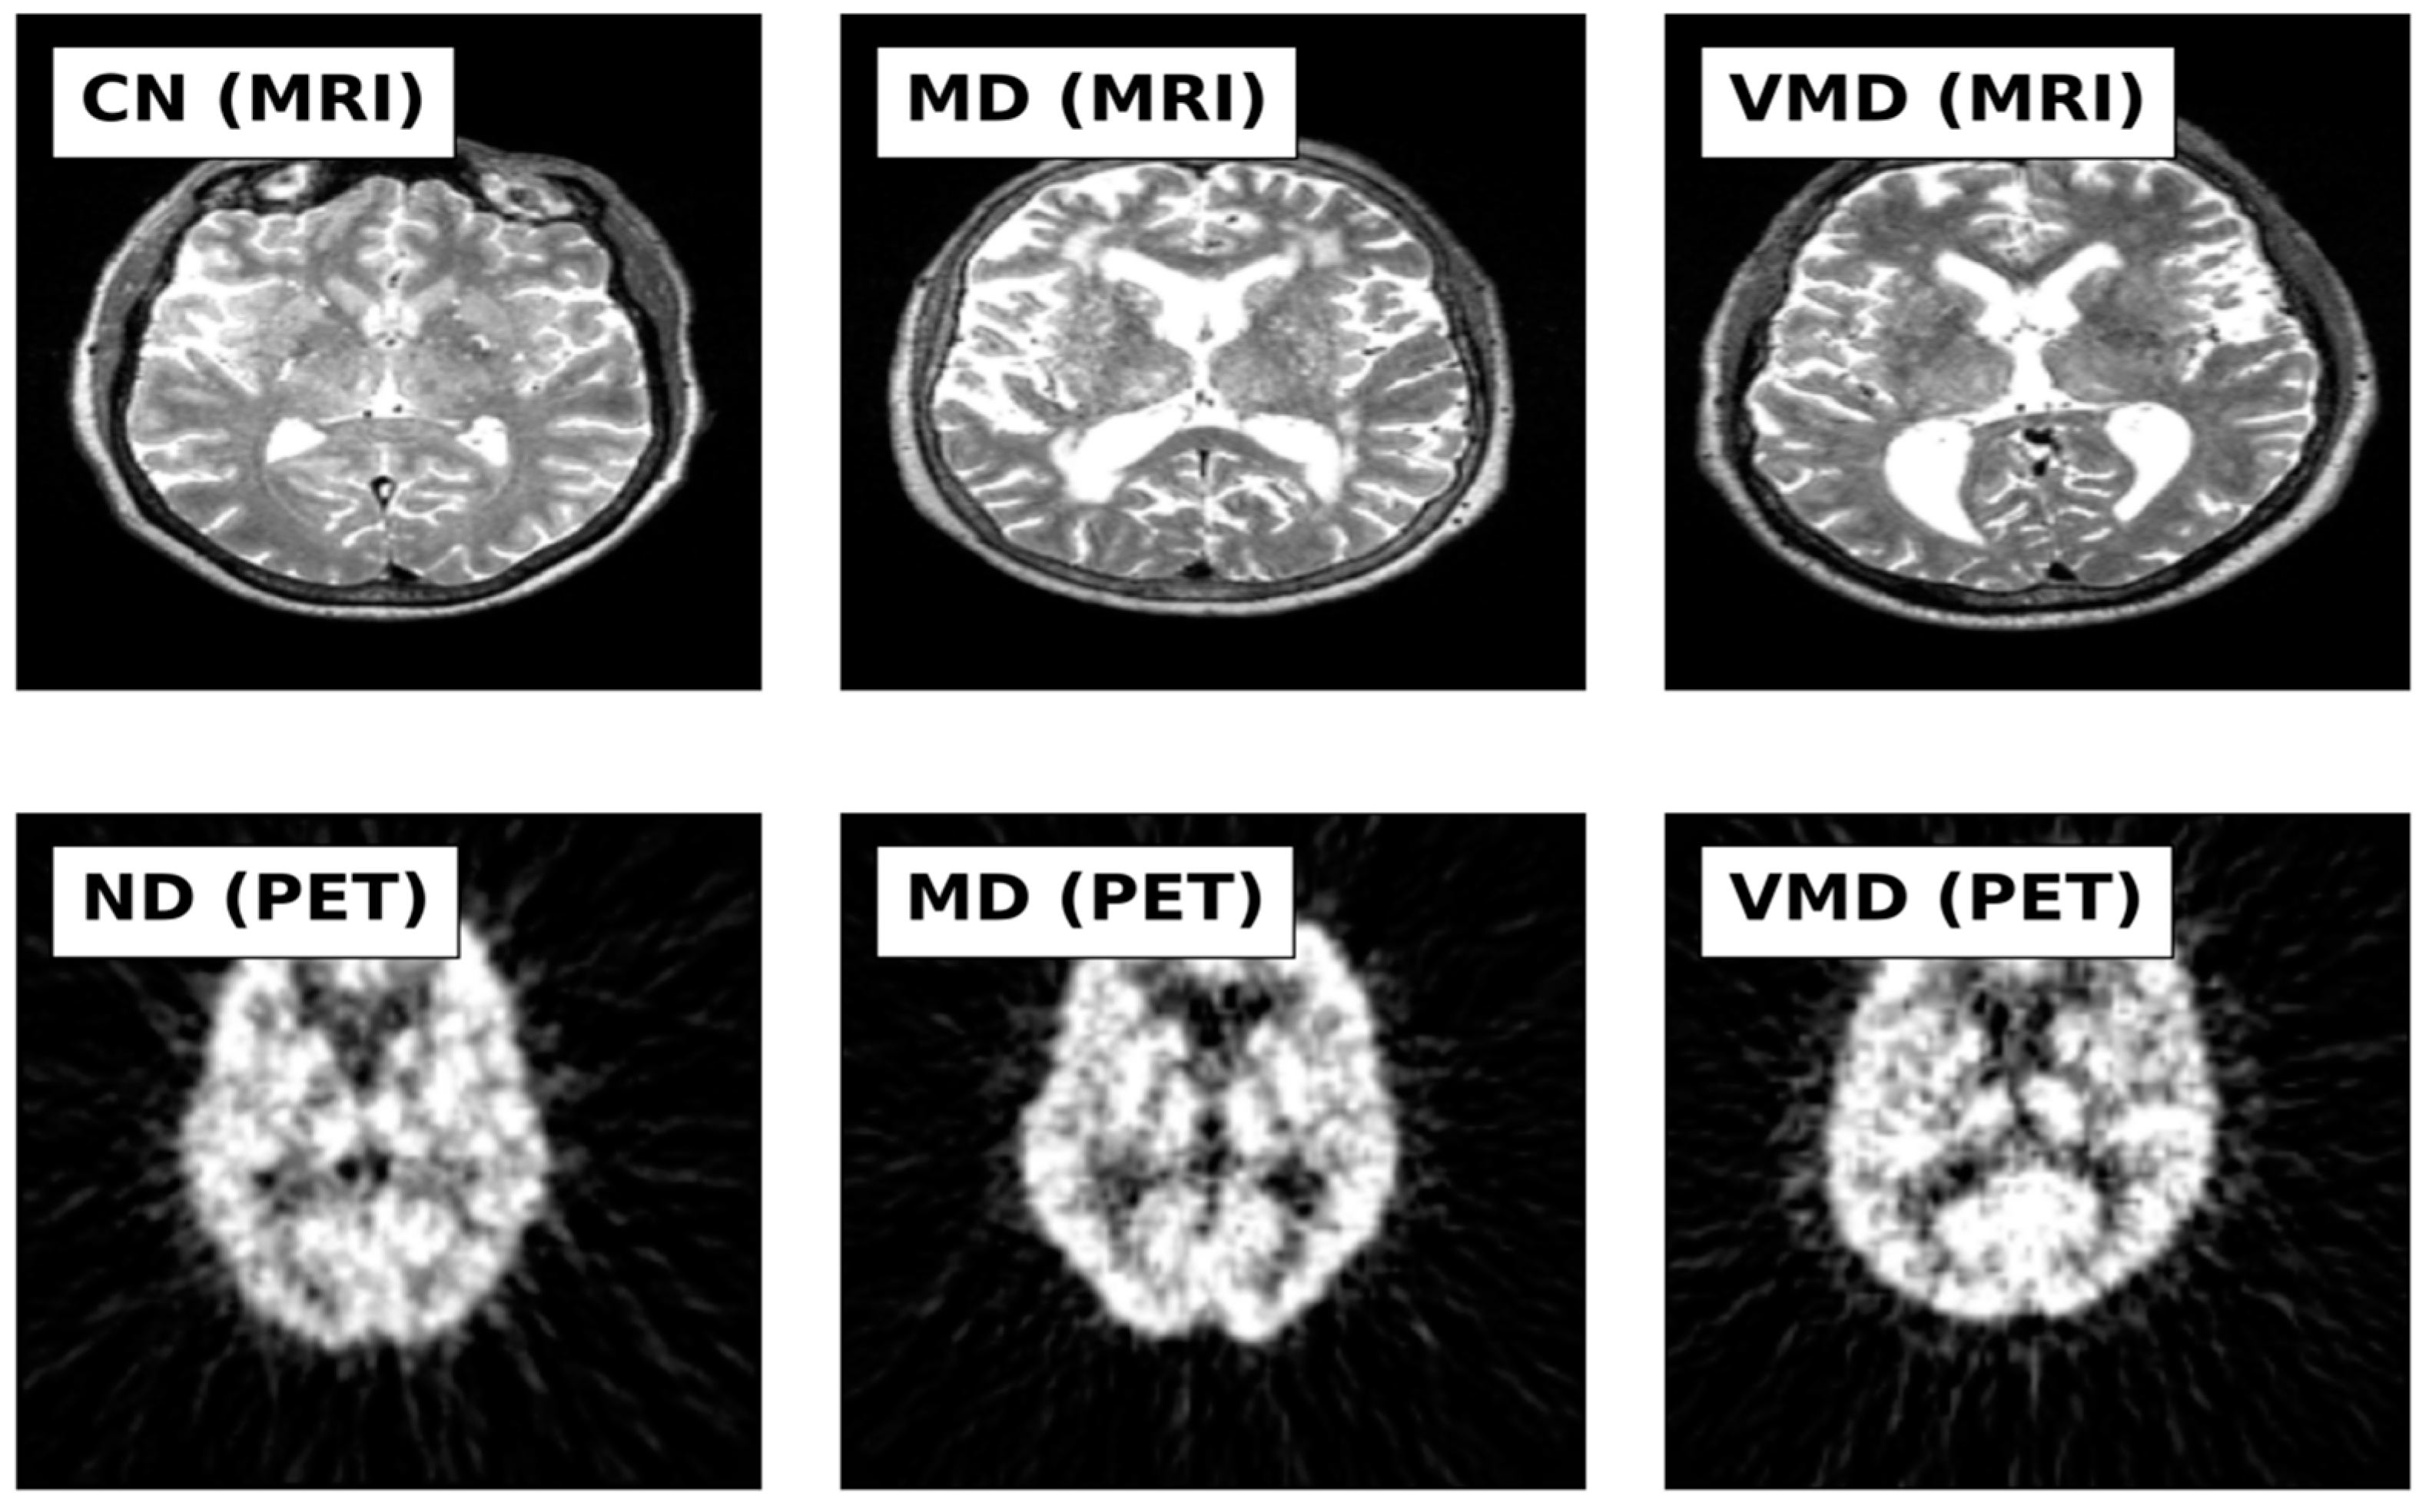

This study utilized MRI and PET images obtained from the official website of Harvard University (http://www.med.harvard.edu/AANLIB/home.html (accessed on 15 September 2023)), the ADNI website (https://adni.loni.usc.edu (accessed on 15 September 2023)), and the OASIS website. The brain images under consideration are categorized into two distinct stages, namely Cognitive Normal (CN) and Alzheimer’s Disease (AD). 50 images of each of the stages are downloaded from each website, making a total of 300 images. PET images are in red, green, and blue (RGB) while MRI images are in black and white. Figure 2, Figure 3 and Figure 4 show sample the datasets used from AANLIB, ADNI, and OASIS database, respectively.

Figure 4.

Sample Images from OASIS Database.